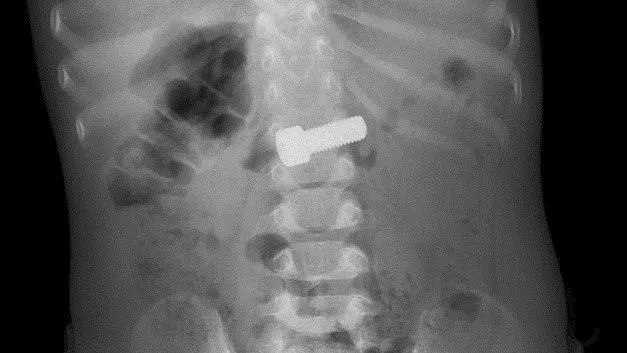

Проглотившего металлический болт ребенка спасли в медцентре Рошаля

Специалисты Детского научно-клинического центра имени Л. М. Рошаля помогли годовалому ребенку, который проглотил металлический болт. Юного пациента привезли в медицинское учреждение на машине скорой помощи.

В приемном отделении ребенку сделали рентген, который подтвердил наличие инородного тела. Врачи, учитывая размер болта, приняли решение провести вмешательство. Объект мог привести к повреждению стенок желудка или кишечника и спровоцировать перитонит.